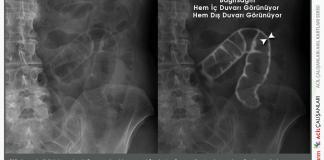

Çift Duvar Belirtisi (Rigler’s Sign)

Rigler belirtisi, aynı zamanda çift duvar belirtisi olarak da bilinir, karın grafisinde (röntgeninde) görülen bir pnömoperiton (karın içinde serbest hava) bulgusudur. Bu bulgu, gazın...